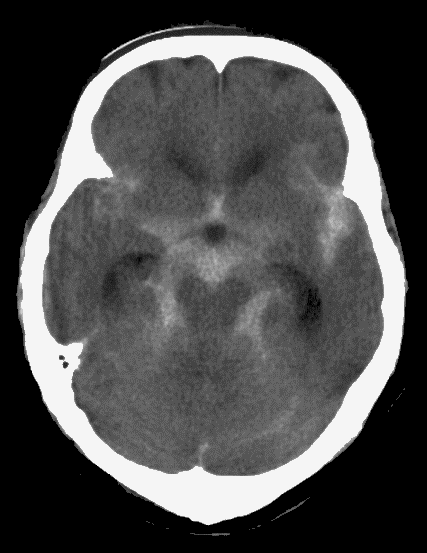

くも膜下出血のCT

【くも膜下出血のCT】